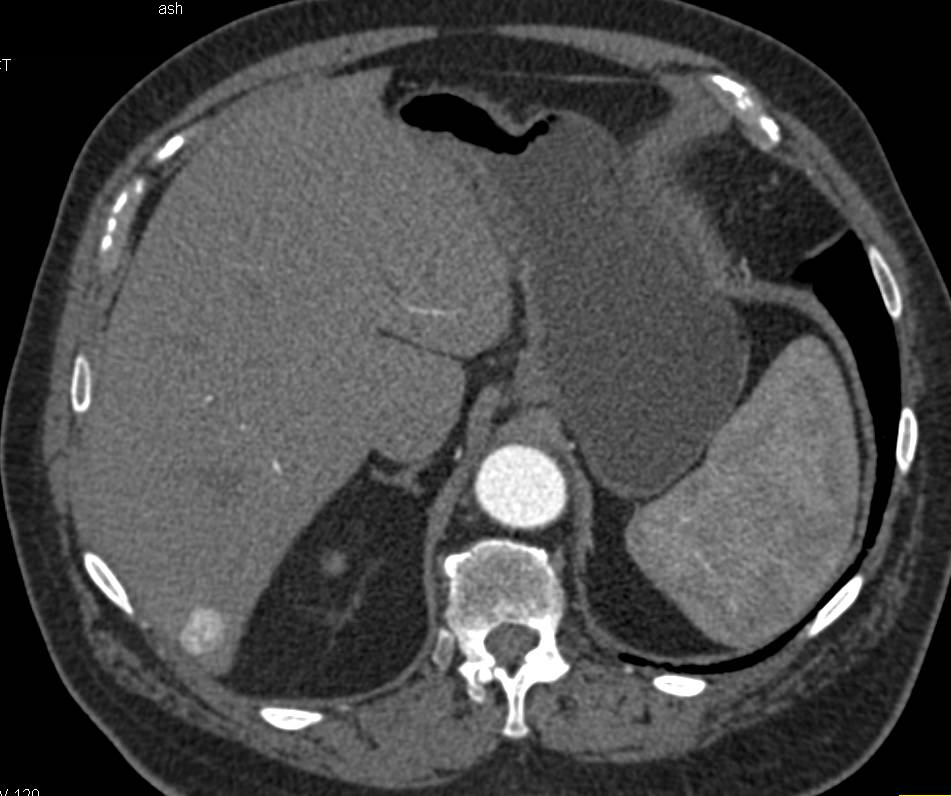

Abscess in the Gallbladder Fossa